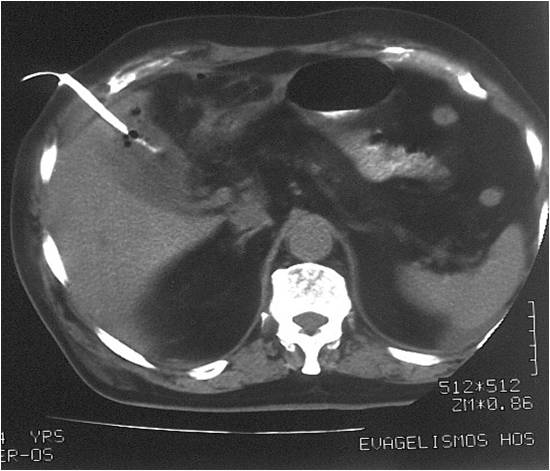

- Large abdominal abscess post- pancreatic surgery

- Successful drainage